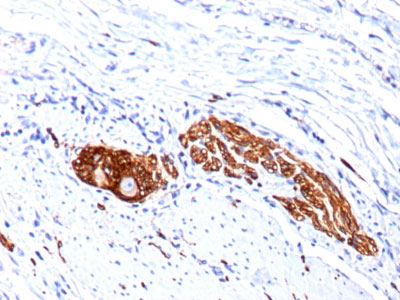

Formalin-fixed, paraffin-embedded human Colon Ganglion stained with CD56 Monoclonal Antibody (123C3.D5 + 123A8)

Formalin-fixed, paraffin-embedded human Lung Carcinoma stained with CD56 Monoclonal Antibody (123C3.D5 + 123A8) |